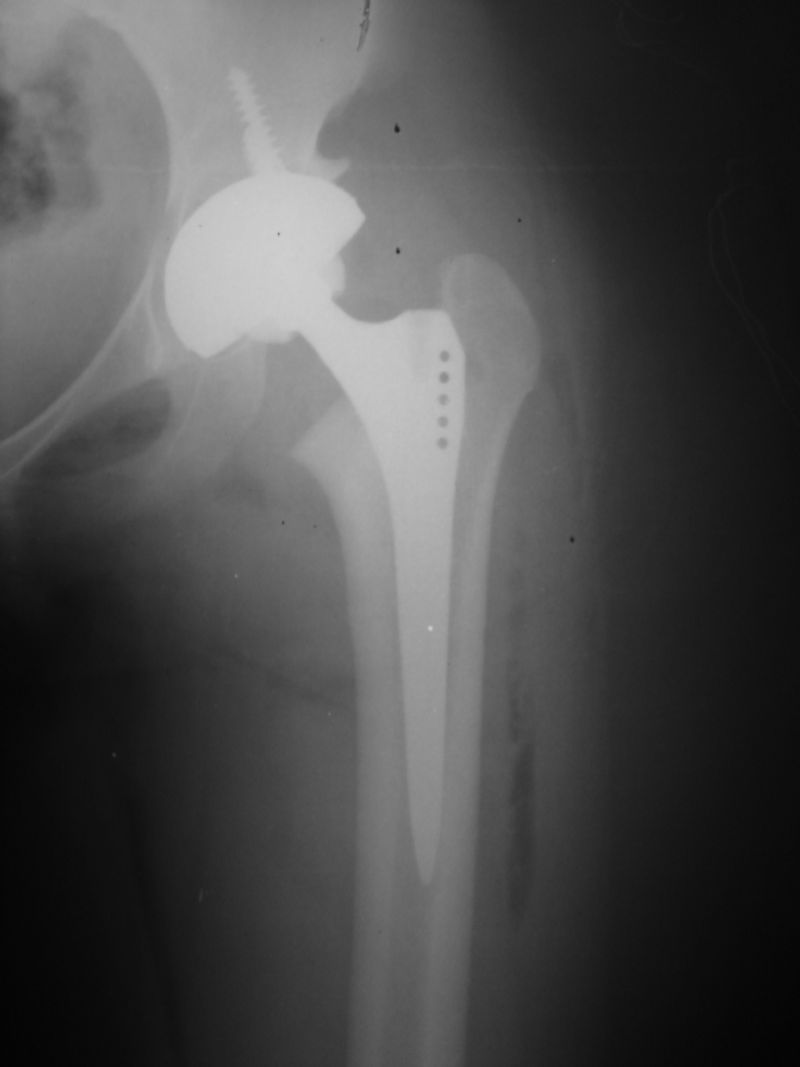

Total Kalça Protezi Örnek Olgular